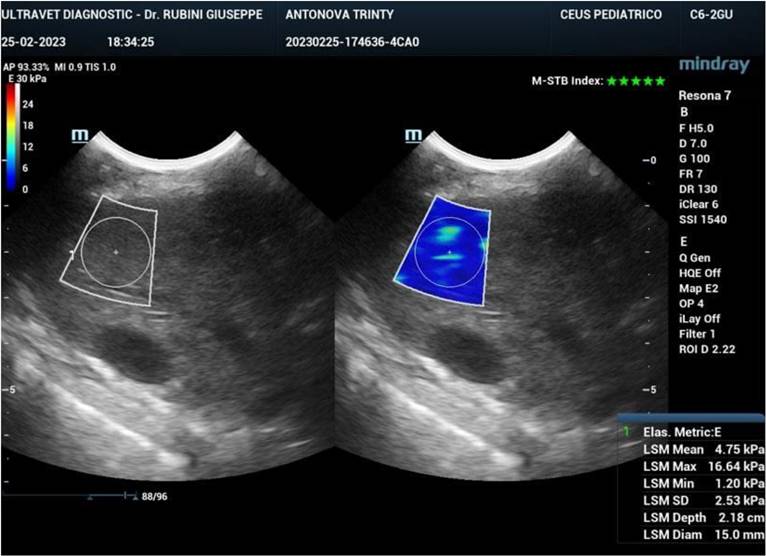

Ultrasound elastography (also known as sonoelastography) was used to support the diagnosis and management of diffuse liver disease. Elastography can identify early-stage and advanced liver fibrosis and thus is a major application in clinical liver care. In addition, elastographic characterization of focal liver lesions and evaluation of clinically significant portal hypertension can potentially be clinically useful and are areas of active clinical research. Currently, the accepted liver fibrosis staging reference standard is the histopathologic evaluation of non-focal liver biopsy specimens. However, liver biopsy has some limitations: 1) liver biopsy is invasive, 2) liver biopsy is costly, and 3) inter-observer variability limits the clinical interpretability of liver biopsy samples. To this end, 34 dogs treated with exosomes were followed also by sonoelastography to evaluate the presence and reduction of fibrosis after 180 days from the first injection of exosomes. As reported in Figure 7, fibrotic tissue with alteration of blood flow (highlighted in the circle) is visible before the treatment. Figure 8 shows that the fibrotic event is no more present and the portal vein blood flow has recovered after 180 days from the first injection of exosomes.

Figure 8

Sonoelastography of the canine liver 180 days after injection of autologous exosomes. No fibrotic tissue is visible, and the portal vein blood flow is restored.

Nanotheranostics Image